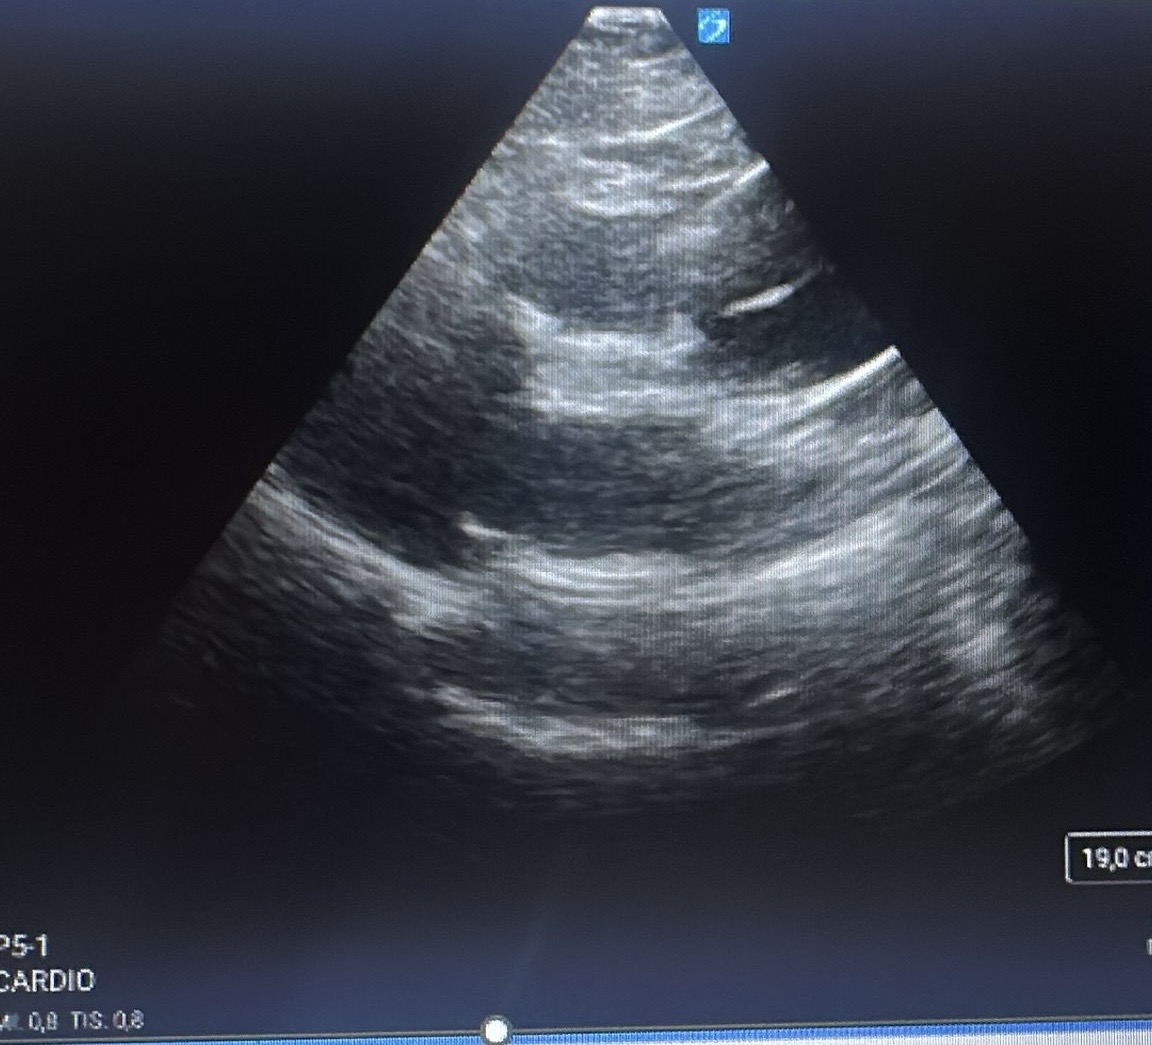

Y justo antes de bajarlo al escáner, le realizamos una ecografía cardíaca a pie de cama donde se visualizó una disección de aorta en la raíz y donde se completó el estudio con un angioTC (progresaba de cayado hasta región abdominal) y cambió totalmente el enfoque del cuadro.